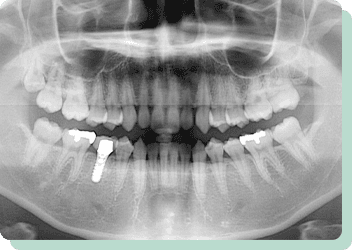

この患者様は右下に1本永久歯の先天性欠如がありました。ブリッジ・入れ歯・インプラント、いずれの処置法も可能ですが、前後の歯に負担をかけたくない、しっかりと左右で噛みたいという希望であったため、インプラント治療にて対応しました。

リスク:疼痛・咬合時痛・冷水痛・出血・インプラント手術による歯ぐきなどの損傷・インプラント周囲炎など

費用:インプラント治療1本あたり440,000円